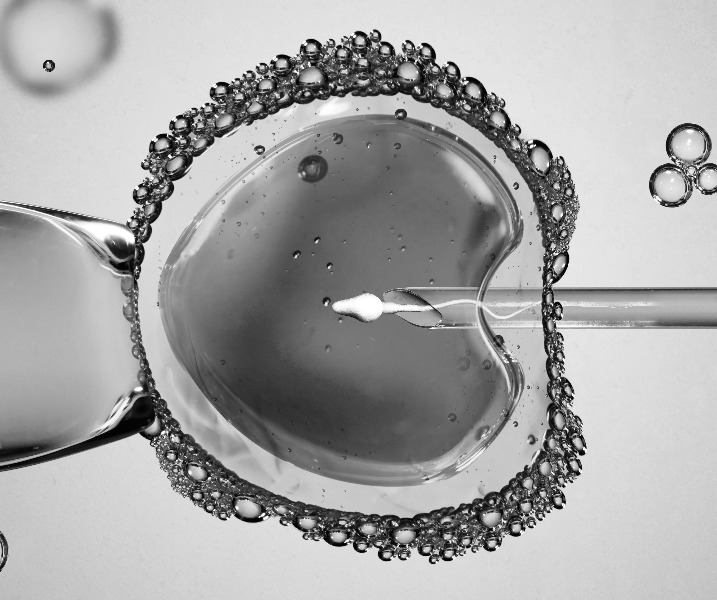

A FIV com ICSI (Injeção Intracitoplasmática de Espermatozoides) é uma variante da FIV tradicional, na qual um único espermatozoide é injetado diretamente no óvulo para facilitar a fertilização. Isso é especialmente útil quando há problemas de qualidade ou quantidade de espermatozoides.

- Injeção dos espermatozoides: Um único espermatozoide é injetado diretamente em cada óvulo.